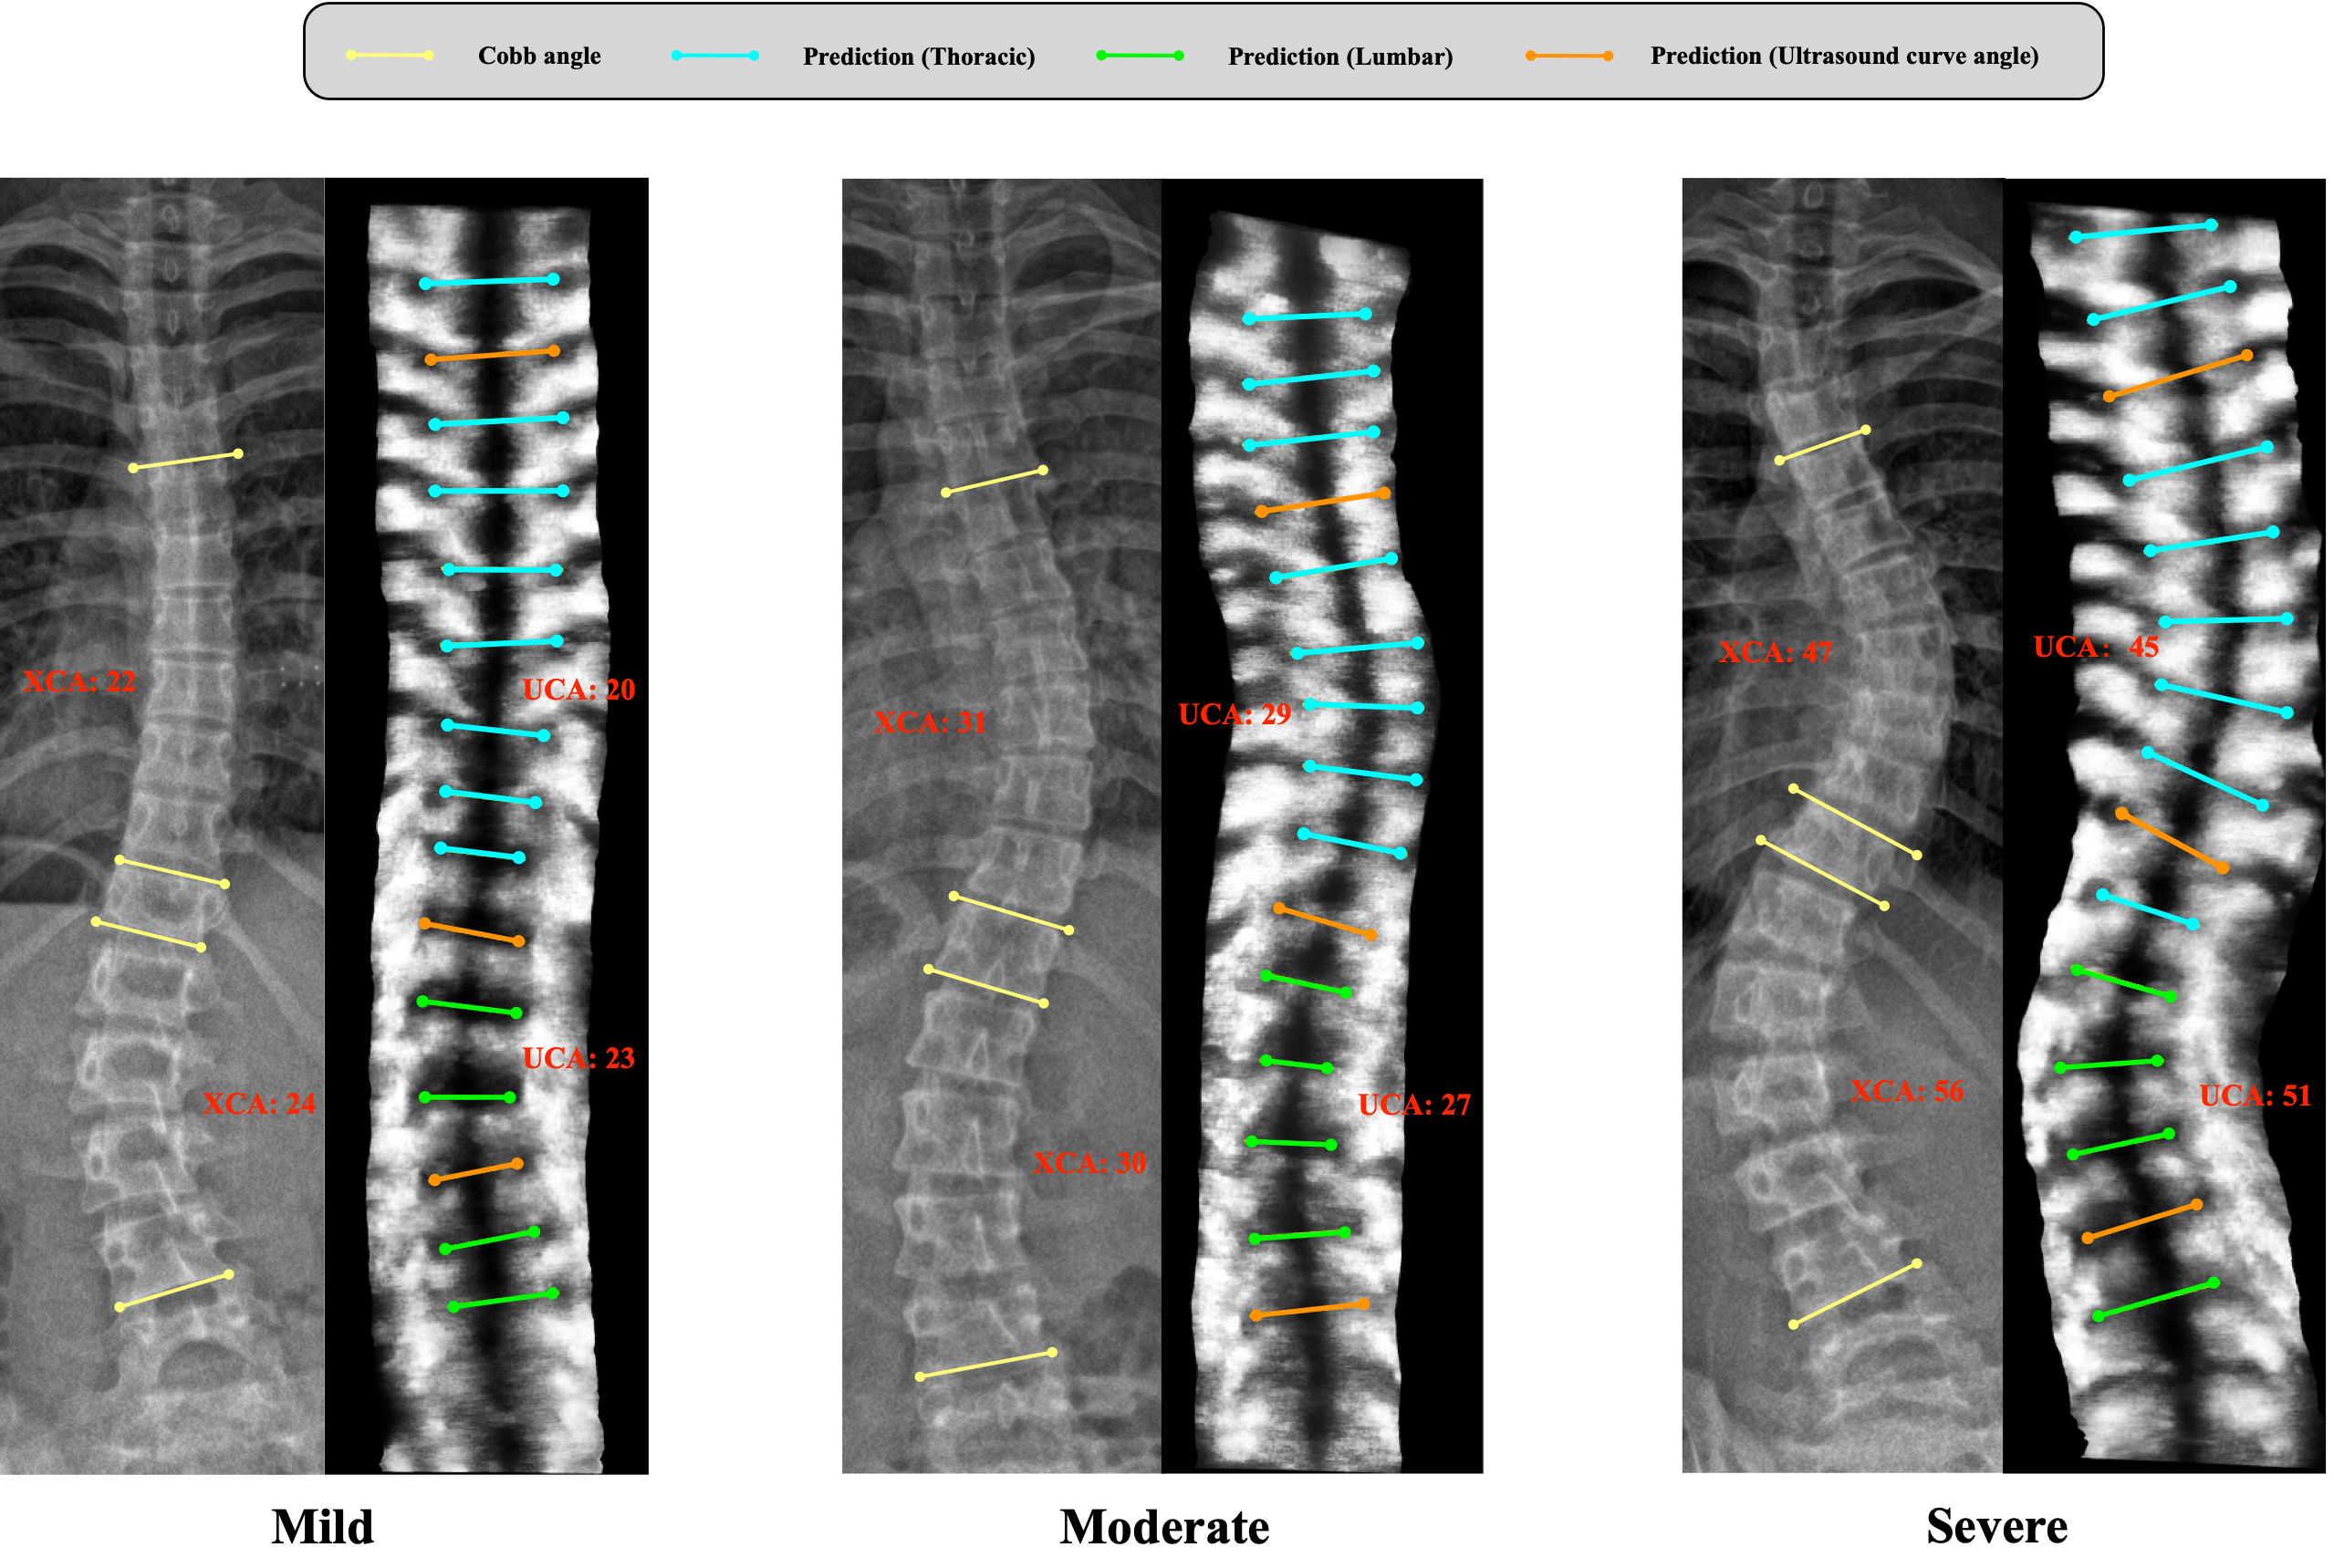

Figure 8: . Visual comparison between Ultrasound Curve Angle (UCA) and X-ray Cobb angle (XCA) in different degrees of scoliosis.

4.5 Comparison with Cobb Angle

In this section, we evaluate the correlation between automatic ultrasound curve angle and X-ray Cobb angle. The linear regression analysis and Bland-Altman plots are shown in Figure.7. Figure.8 visualizes the result between predicted UCAs and Cobb angles for the same patients. The results reveal a strong correlation between the automated UCA and the Cobb angle, evidenced by an R2 value of 0.858. The study result closely aligns with the previously reported results of the comparison between manual UCA and Cobb angle (R2=0.888) [7]. The Bland-Altman plots indicate an overall mean difference of 1.31 degrees, exhibiting good agreement between the predicted UCA and the Cobb angle. Seventy-six percent of UCA (441 out of 580 curves) exhibit a difference within 5° when compared to the Cobb angle. The scaling factor, derived from the linear equation, is determined to be 1.02, indicating a great agreement between automated UCA and the Cobb angle. We observed that the vertebral bodies contributing to the angle measurement may not align consistently between ultrasound and X-ray imaging. This discrepancy arises from the different approaches used in the two modalities. In X-ray, the apex position is first determined, and then line segments are selected on either side of the apex. In contrast, we directly calculate the inclination of each vertebral body in ultrasound, thereby avoiding the potential occurrence of adjacent vertebral bodies being more inclined than the measured vertebral body. Our approach achieves a more accurate and reliable assessment of the vertebral inclination.